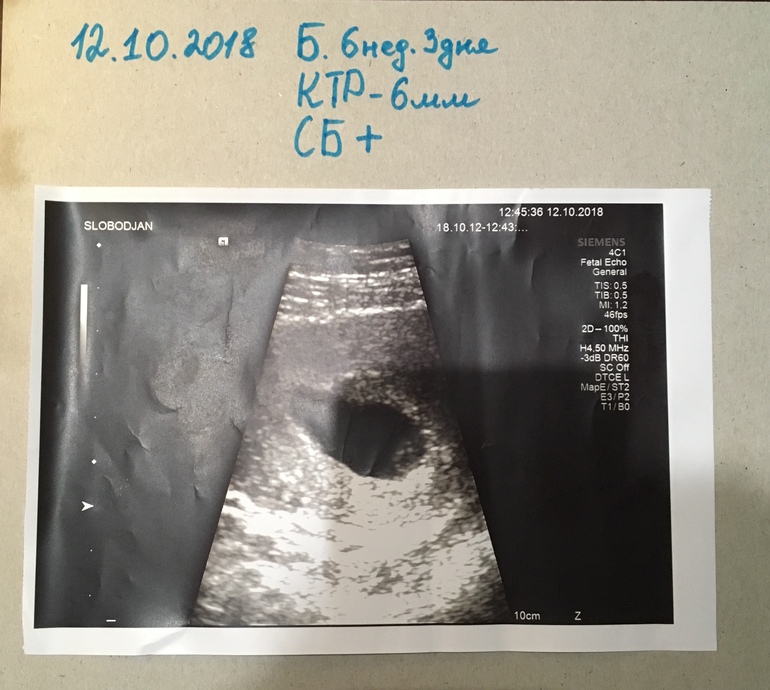

Как прекрасно услышать впервые СБ

Пупсичек мой,12-ого октября мама впервые увидела тебя как ты выглядишь-крошечка моя,когда мне включили твоё сердцебиение я взахлёп ахнула,так что аж аппаратура в УЗИ кабинете это передала на все улицы города🤭!Мама была тронута безумно сильно😍😇

В этот день мы сообщили твоей сестрёнке что будет у неё братик или сестричка!Она была очень-очень счастлива от этой новости,и задавала мне множество вопрос: кто ты-девочка или мальчик?когда ты родишься?какой(ая) ты сейчас?можно ли я куплю первый костюмчик?...😇😘с нетерпением ждала встречи с тобой хотя бы увидеть тебя на мониторе,просила чтоб в следующий раз взяла её с собой на УЗИ🤗😘